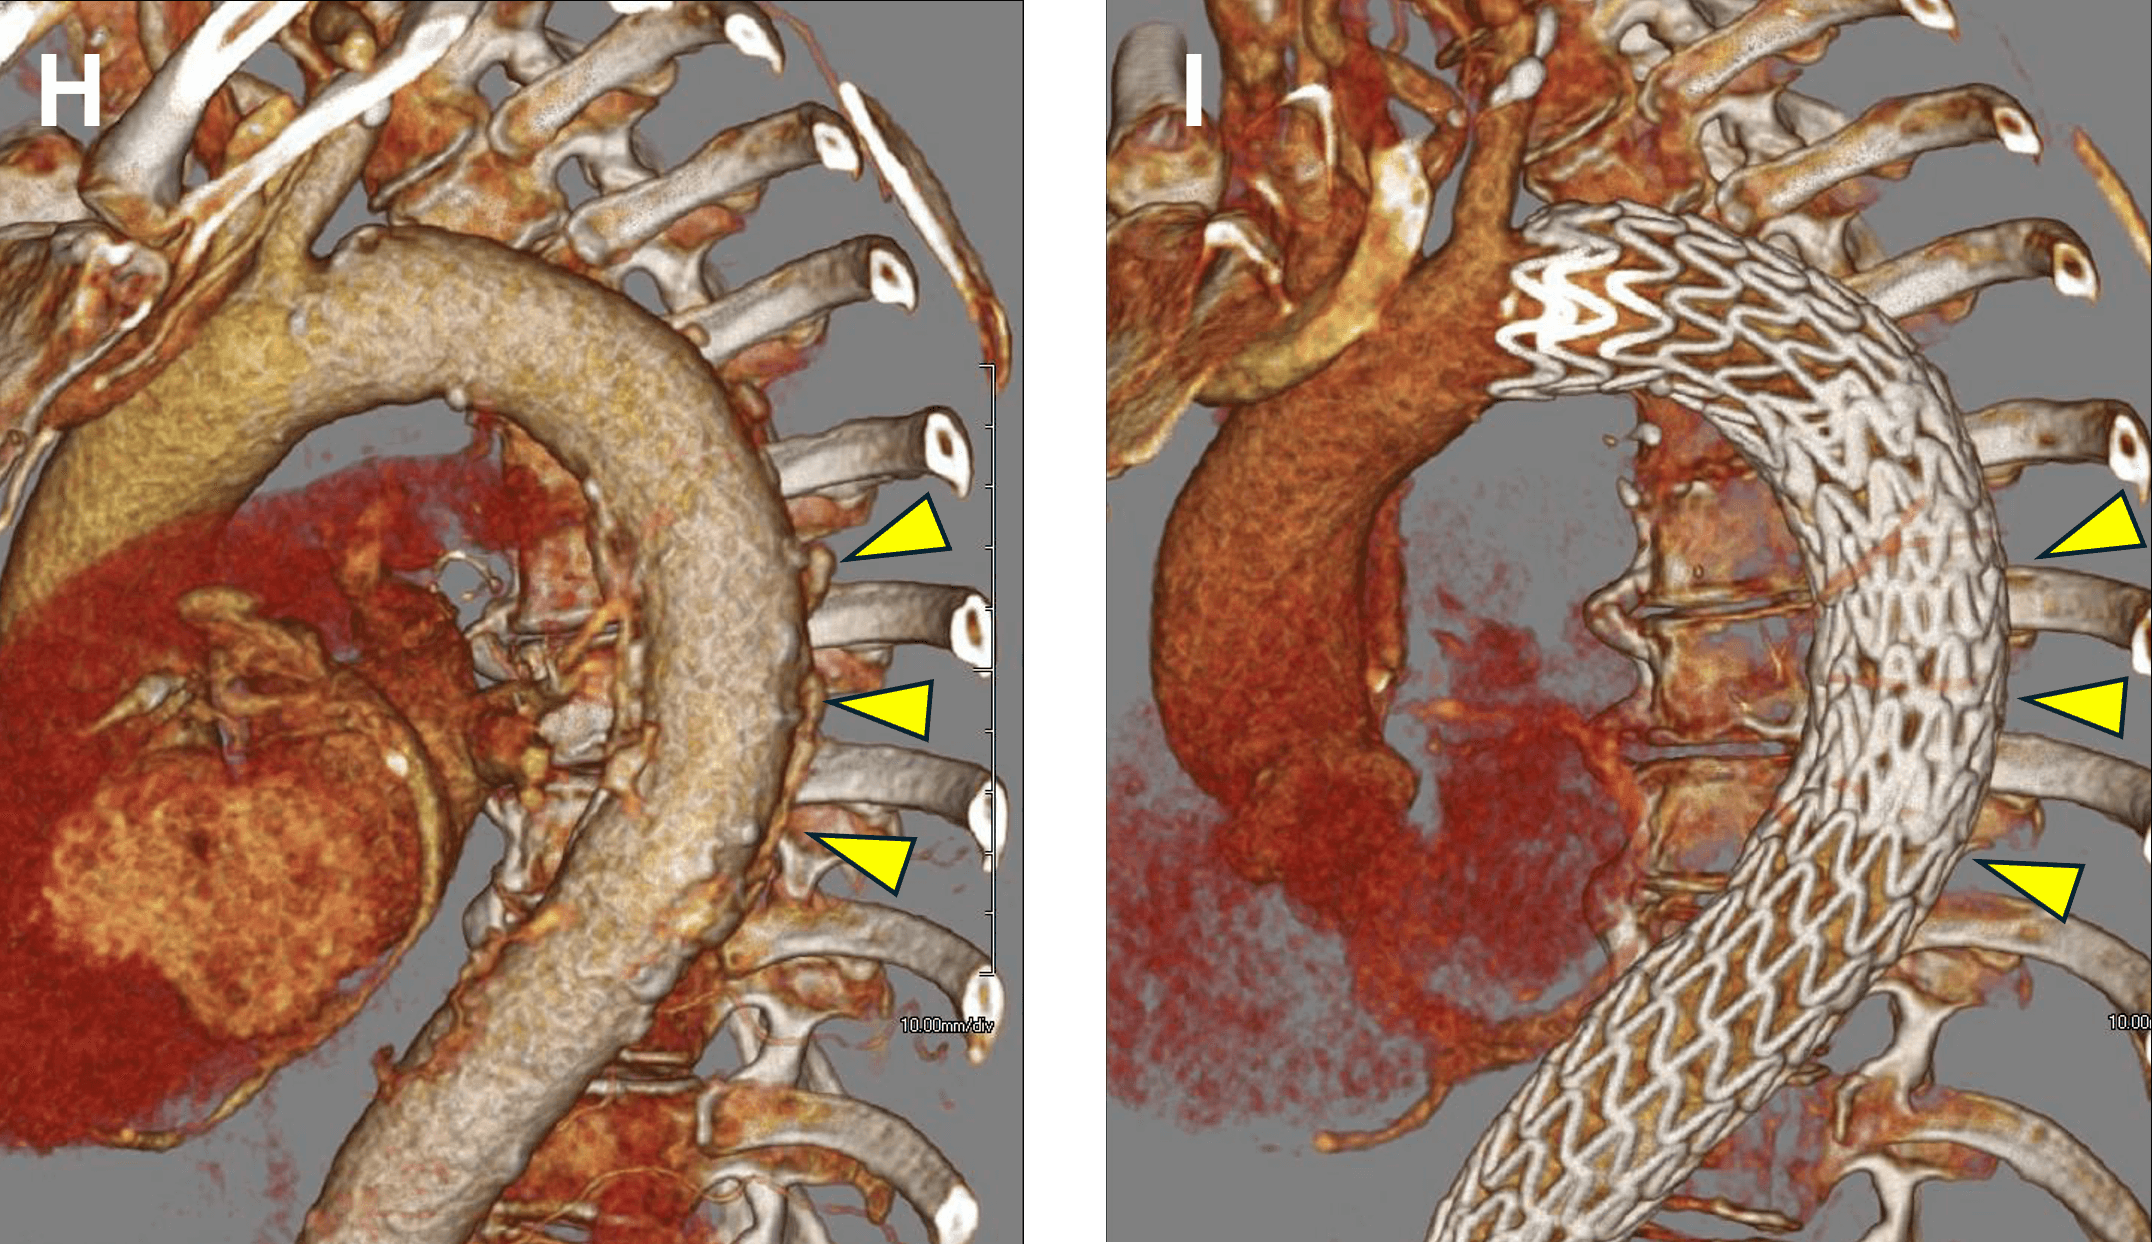

Figure E-F: Treatment of Intramural Hematoma (IMH)

Figure E. Sagittal MPR image before treatment shows ulcer-like lesions and adjacent intramural hematoma (arrowheads).

Figure F. Status post Thoracic Endovascular Aortic Repair (TEVAR). The ulcer-like lesions are no longer identified, and the IMH / aortic mural thickening has decreased (arrowheads).

Figure G-H: Treatment of Intramural Hematoma (IMH)

Figure G: Sagittal subvolume VR image before treatment shows ulcer-like lesions (arrowheads).

Figure H: Sagittal subvolume VR image after treatment. The patient is status post Thoracic Endovascular Aortic Repair (TEVAR). The ulcer-like lesions are no longer identified (arrowheads).